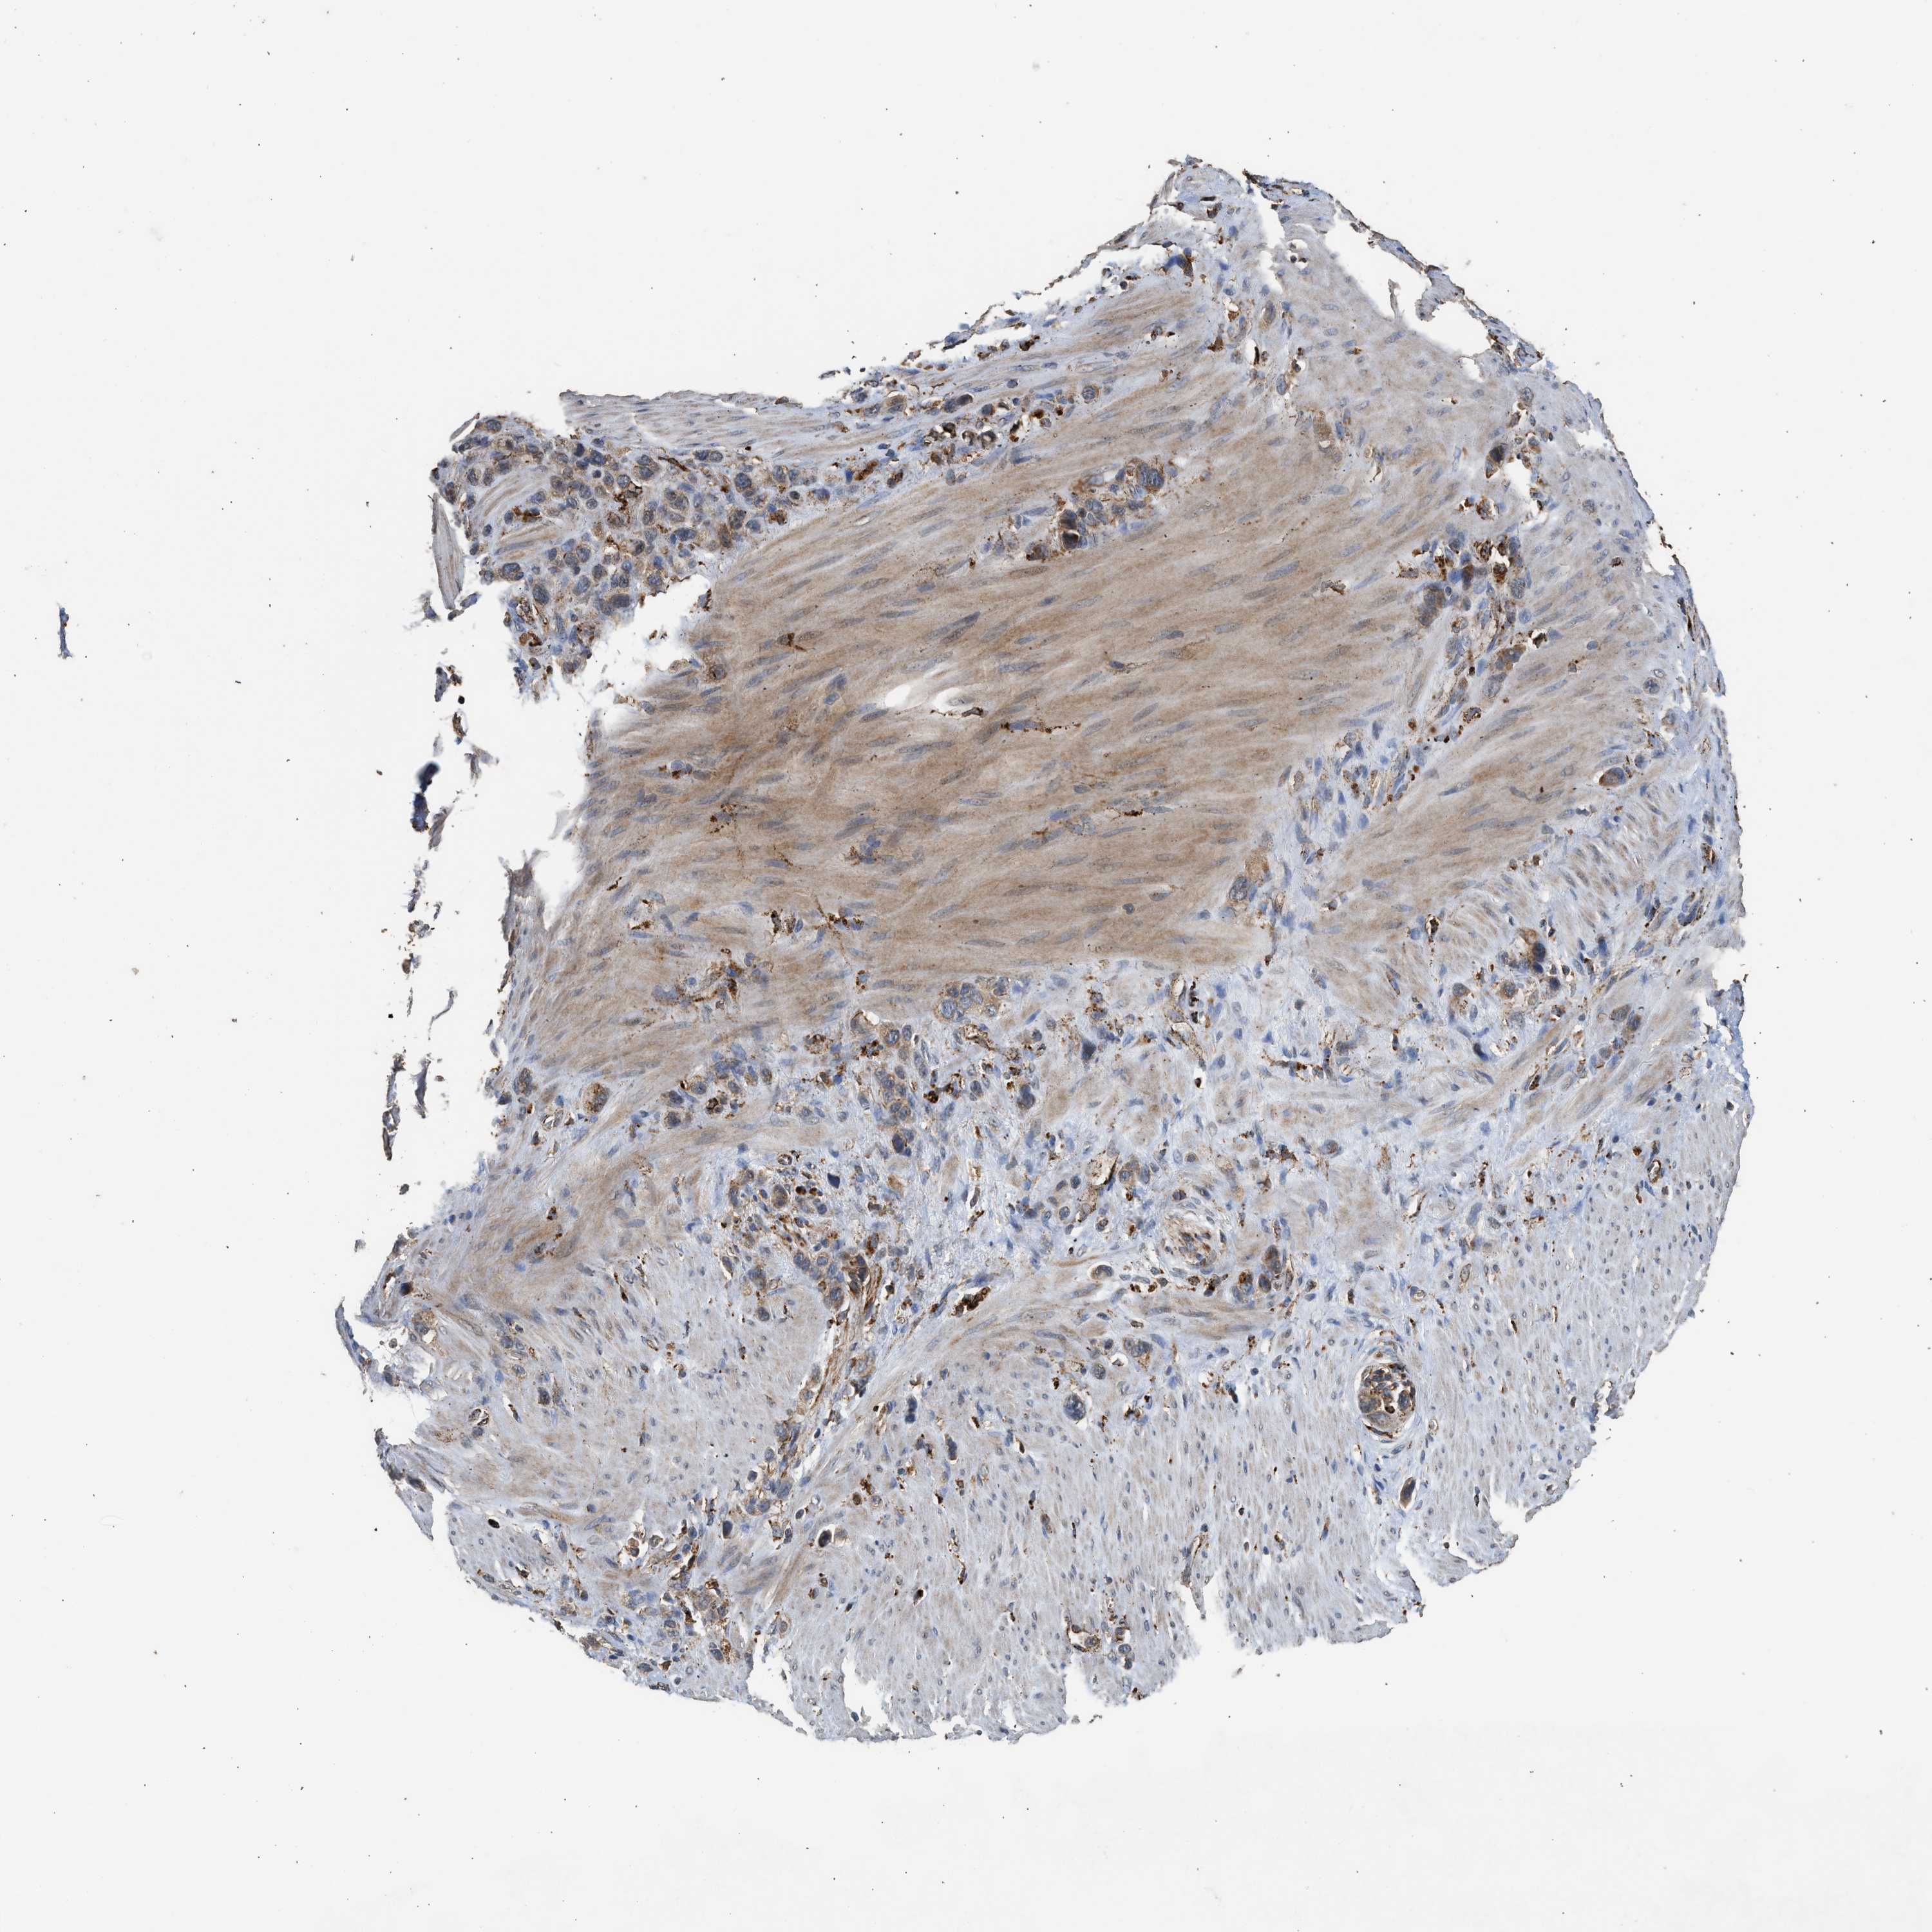

STOMACH CANCER - Protein expressioni

A mouse-over function shows sample information and annotation data. Click on an image to view it in a full screen mode. Samples can be filtered based on level of antibody staining by selecting one or several of the following categories: high, medium, low and not detected. The assay and annotation is described here.

Note that samples used for immunohistochemistry by the Human Protein Atlas do not correspond to samples in the TCGA dataset.

Antibody stainingi

Antibody staining in the annotated cell types in the current human tissue is reported as not detected, low, medium, or high, based on conventional immunohistochemistry profiling in selected tissues. This score is based on the combination of the staining intensity and fraction of stained cells.

Each image is clickable and will lead to virtual microscopy that enables deeper exploration of all samples and also displays staining intensity scores, fraction scores and subcellular localization as well as patient and tissue information for each sample.

Antibody CAB017112

Staining

High

Medium

Low

Not detected

Intensity

Strong

Moderate

Weak

Negative

Quantity

>75%

75%-25%

<25%

None

Location

Nuclear

Cytoplasmic/membranous

Cytoplasmic/membranous,nuclear

Adenocarcinoma, NOS

Adenocarcinoma, High grade